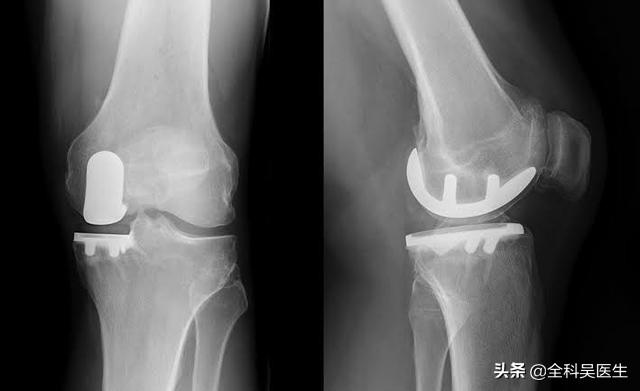

● Si les symptômes de l'articulation sont particulièrement sévères et que le patient a développé une...Déformations articulaires évidentesSi vous êtes incapable de marcher normalement, si vous ressentez des douleurs articulaires importantes lorsque vous marchez plus de 500 mètres et si vous êtes gravement affecté par des douleurs au repos ou pendant votre sommeil, il y a une indication pour une prothèse articulaire.L'arthroplastie du genou peut être le seul moyen d'aider complètement le patient.。

8. traitement chirurgical :Si les lésions du genou sont graves, elles peuvent également être réparées par chirurgie arthroscopique.

9. remplacement du genou :Si l'arthrose a entraîné une déformation évidente de l'articulation, qui affecte gravement le traitement de la vie du patient, le moment est venu de résoudre complètement le problème du patient par la mise en place d'une prothèse de genou.

Apparition tardive : articulations artificielles pour soulager la douleur sévère

Aux stades avancés de la maladie, le cartilage du patient est presque usé. Sans l'amortissement du cartilage, les os frottent directement l'un contre l'autre. À ce stade, les seules options sont de remplacer l'articulation par une prothèse ou de procéder à une arthrodèse, qui est rarement utilisée car elle peut affecter gravement la mobilité du patient après l'opération.